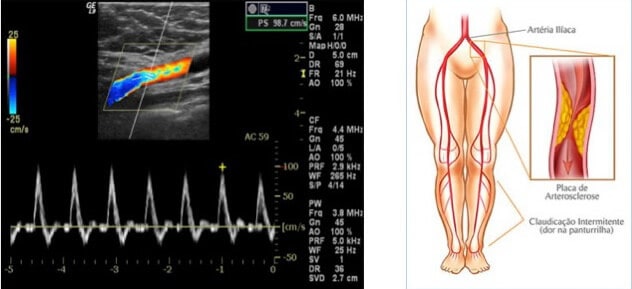

Este exame de ultrassom Doppler serve para auxiliar no rastreamento de doença isquêmica periférica, na seleção de pacientes para exame invasivo, no controle de tratamento de afecções arteriais de membro inferior e no planejamento cirúrgico. Este exame é utilizado para monitorar reconstruções arteriais e enxertos vasculares, por exemplo.

Doppler Colorido Arterial Periférico